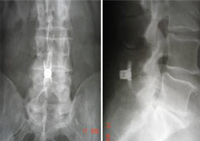

Implantes dinámicos percutáneos para lumbalgia crónica por síndrome facetario